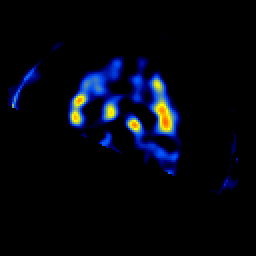

SPECT TL Study #7 -- Slice #49

[Home][Help][Clinical][Tour 1][Tour 2][Tour 3] Slice 49